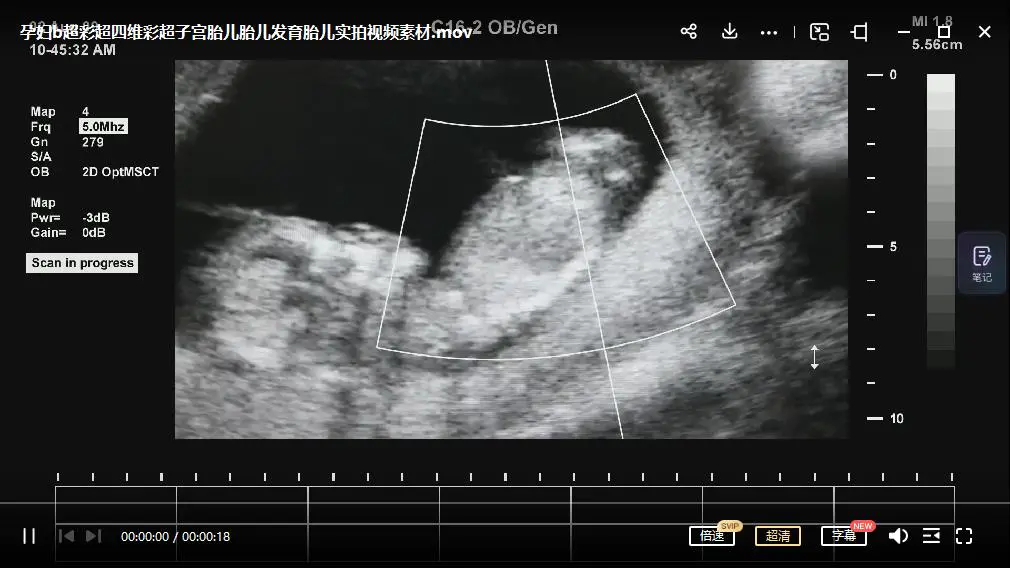

此项目包含短视频无人直播变现玩法及淘客变现玩法

项目包含所需的素材,软件,教程及变现原理